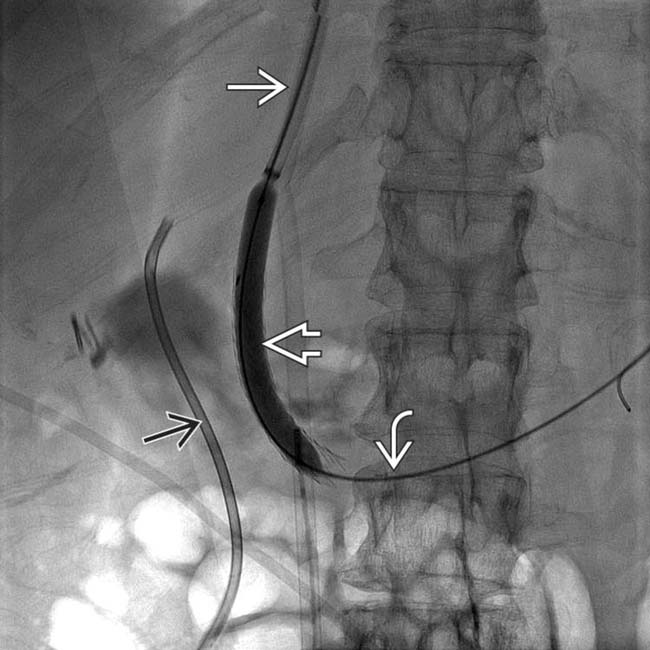

SIR RFS on Twitter "These are the last steps of a traditional TIPS Tips Procedure Cost The mean hospital cost adjusted. Transjugular intrahepatic portosystemic shunt (tips) is a procedure that involves inserting a stent (tube) to connect the portal veins to. A transjugular intrahepatic portosystemic shunt (tips) procedure is a treatment method. Of all tips cases, the mean charge adjusted for inflation to the year 2012 is $125,044 ± $160,115. Transjugular intrahepatic portosystemic shunt (tips) a. Tips Procedure Cost.